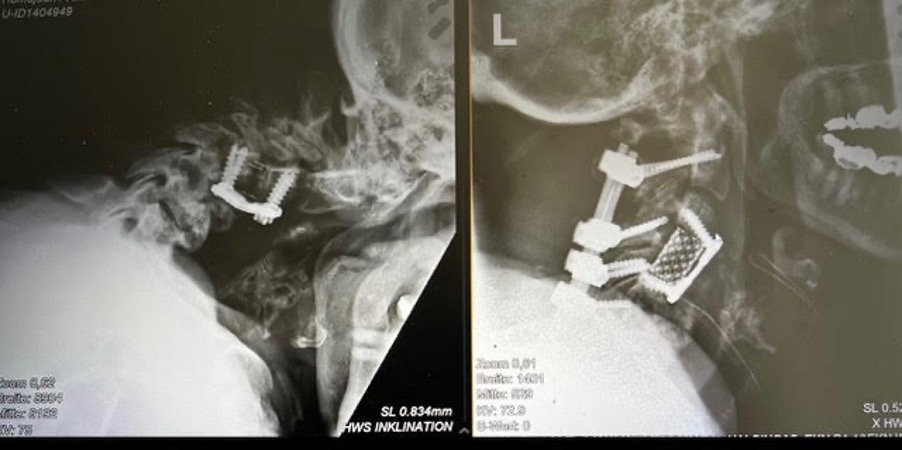

Case I

One patient presented after previous cervical spine surgery performed elsewhere with severe drop head syndrome. She was unable to lift her head and had to support it with her hand to maintain a forward gaze.

Through meticulous reconstructive planning and minimally invasive surgical precision, We restored her horizontal gaze, spinal alignment, and independent mobility. The procedure was completed without complications, allowing the patient to regain not only proper posture but also a significantly improved quality of life.